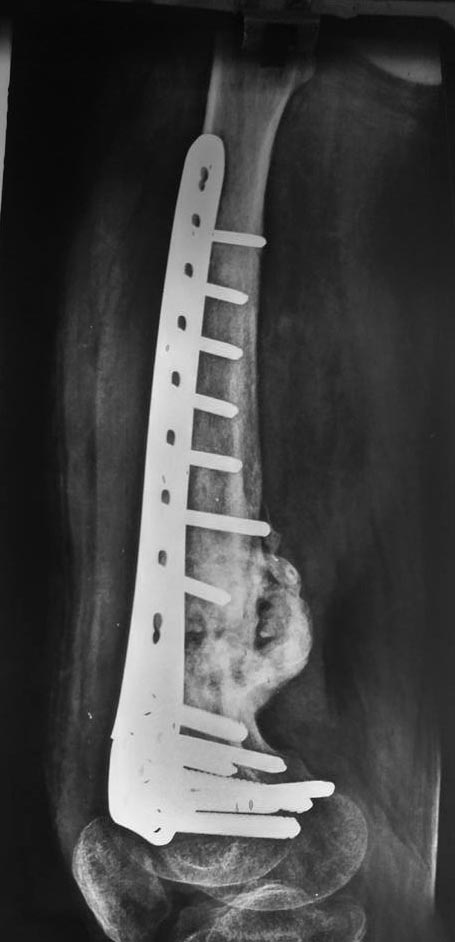

[Ortho] Несращение дистального отдела бедра

Боковая проекция.